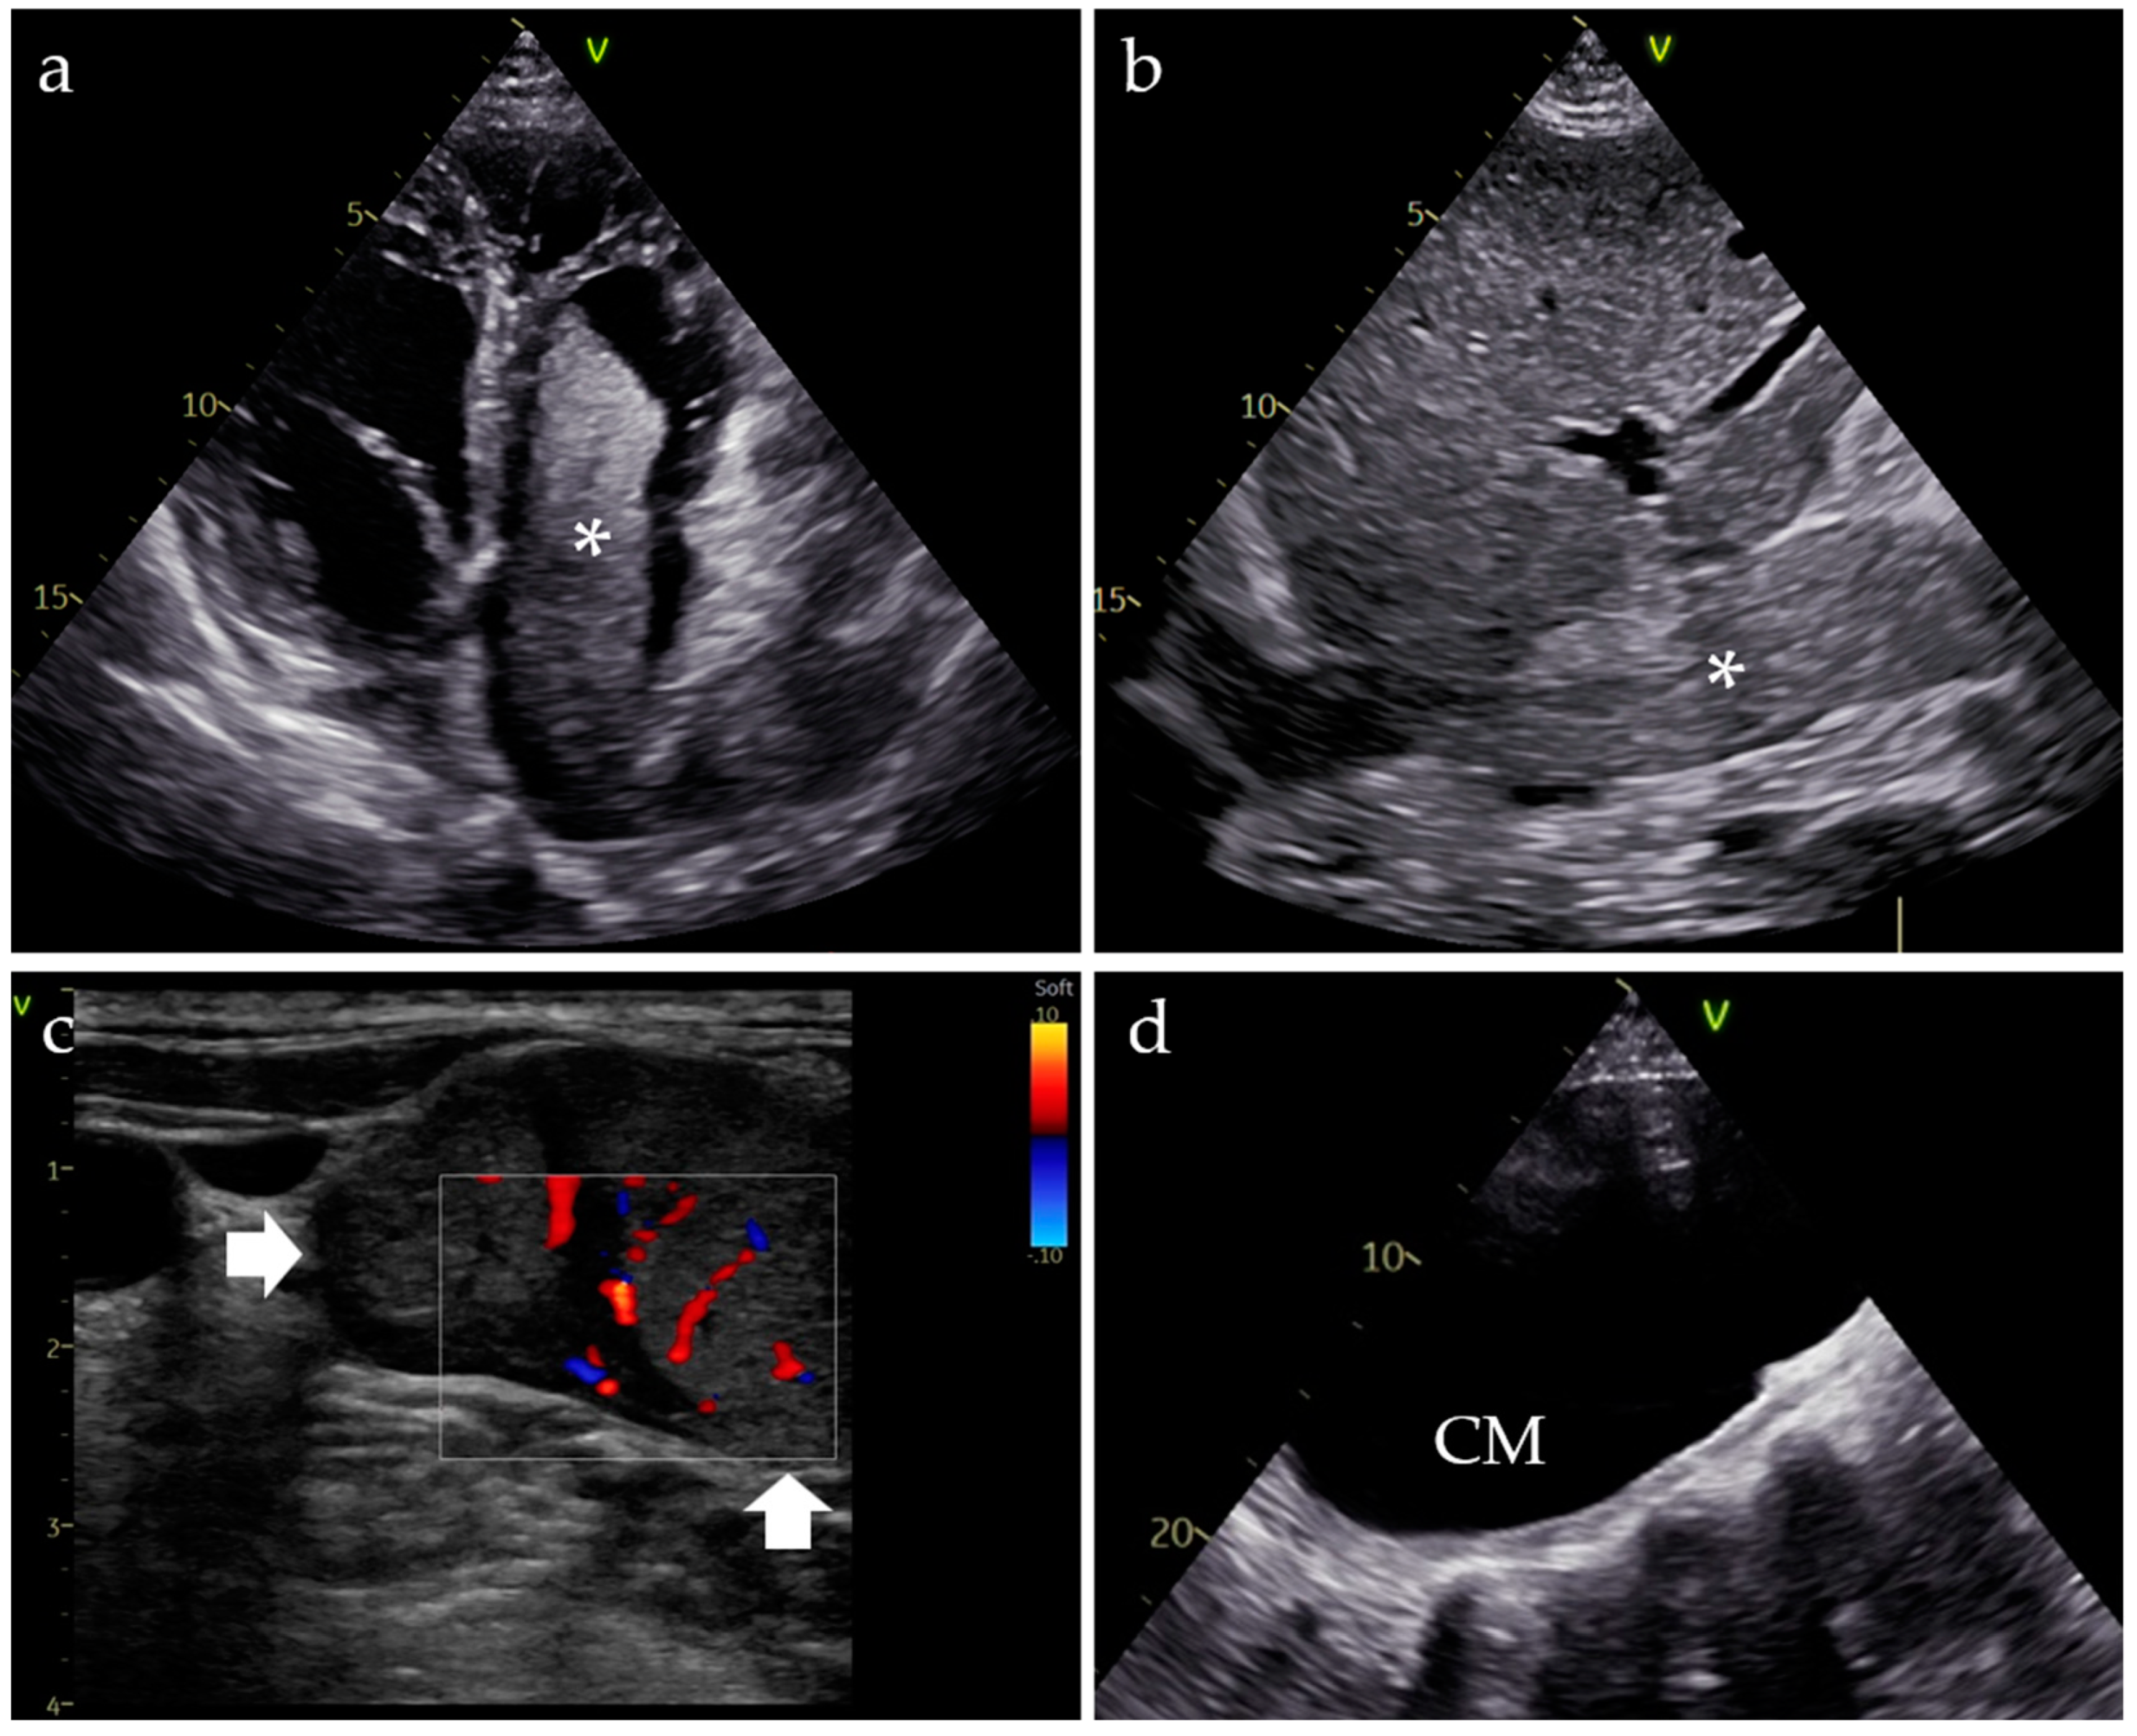

1.3. Diagnostic Assessment

2.2. Inferior Vena Cava Thrombosis